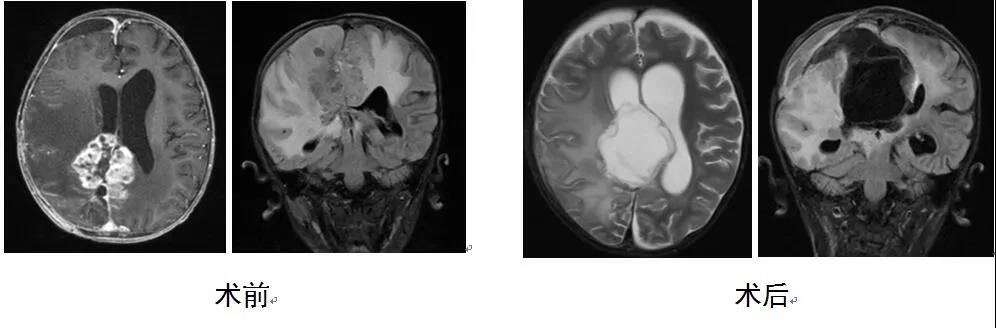

还差一个月满3岁的涵涵有点小调皮,一点不认生,即便是第一次进到病房这种陌生环境也举着手机旁若无人的聊天。涵涵是在4个月前被父母发现左手左脚活动减少的,之后到成都检查就发现颅内长了肿瘤。涵涵父母经过多方打听了解到任主任从北京回到了我们医院,于是慕名前来就诊。复查的结果并不十分乐观,因为这是一个位于专业术语称之为基底节区的肿瘤,这一类肿瘤最大的术后风险就是对侧肢体的瘫痪,这对于一个尚不满3岁的幼儿来说不啻于毁灭性的打击。但不幸中仍然有万幸,涵涵长的脑瘤极有可能是一类常见于小儿的低级别胶质瘤,如果手术充分全切则有望获得治愈。在任主任耐心的讲解和鼓励之下,涵涵父母终于将小女儿送进了我们科的病房。无论是术前手术切口的设计还是手术入路的选择,任主任都全程参与方案制定,甚至在手术中,从切皮开颅到切除肿瘤,任主任都全程亲力亲为,亲自掌控手术的每一步,目的都是为了将手术对患儿的创伤和打击降到最低,因为小儿患者对术中失血以及脑损伤的耐受程度远低于成人。

手术的结果是令人欣慰的,在出血不足100ml的情况下全切肿瘤,而且从术后的影像学上看肿瘤周边重要的脑组织结构几乎毫发无损,术后的病理结果也证实了术前的预判,因此涵涵的病就可以称作临床治愈了。术后的涵涵虽然出现了意料之中的对侧肢体力弱,但在术后对症的治疗和精心的护理之下,涵涵左侧的手脚开始迅速恢复,从一开始的无力抬起,到一周后的可以举高高,再到半个月后可以在父母的搀扶下下地活动,术后一个月的时候涵涵就可以完全自己走路了,虽然有点歪歪扭扭。任主任每次听说涵涵的点滴进步,都会发自内心的感慨:小孩儿的恢复能力真的是太强了!这也就是孩子小小身躯内蕴藏的神奇能量!